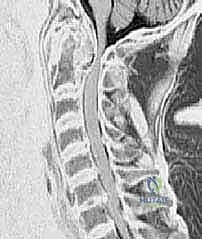

دقة التشخيص والتخطيط الجراحي قبل العملية

النجاح في غرفة العمليات يبدأ في غرفة الفحص. يتبع الأستاذ الدكتور محمد هطيف بروتوكولاً صارماً في التشخيص والتخطيط الجراحي.

- الأشعة السينية الحركية (Dynamic X-rays): التقاط صور للرقبة في وضعية الثني والبسط. هذا الفحص البسيط غالباً ما يكشف عن مدى الانزلاق بين C1 و C2 الذي قد لا يظهر في وضعية الثبات.

- التصوير المقطعي المحوسب (CT Scan) ثلاثي الأبعاد: وهو الفحص الأهم لتخطيط الجراحة. يعطي الدكتور هطيف خريطة دقيقة لتشريح العظام، حجم الكتل المفصلية، ومسار الشريان الفقري، مما يسمح له باختيار حجم ومسار المسامير بدقة المليمتر.

- التصوير بالرنين المغناطيسي (MRI): ضروري لتقييم حالة الحبل الشوكي، وجود أي كدمات أو تلف داخله، وتقييم حالة الأربطة (خاصة الرباط المستعرض).